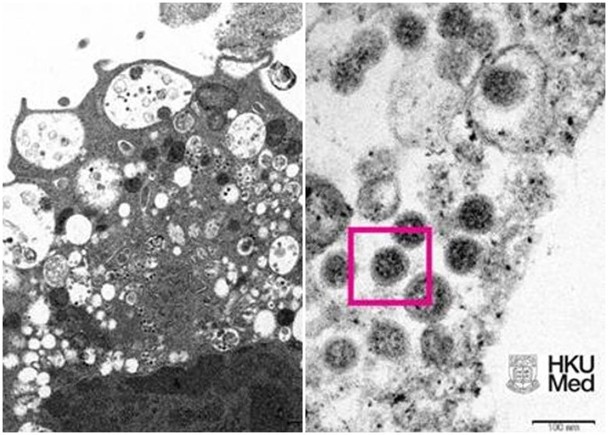

港大公布Omicron在顯微鏡下的樣貌。(港大醫學院提供)

香港大學李嘉誠醫學院今日(8日)發布Omircon變種病毒在顯微鏡下的面貌。其中圖左是低倍電子顯微鏡下感染Omicron後的猴腎細胞(Vero E6)。照片顯示細胞受損,腫脹囊泡,囊泡內含有黑色小病毒顆粒。

圖右則是高倍電子顯微鏡下受感染的Vero E6細胞。照片顯示病毒顆粒,其表面呈現皇冠形的刺突蛋白(見紅框)。